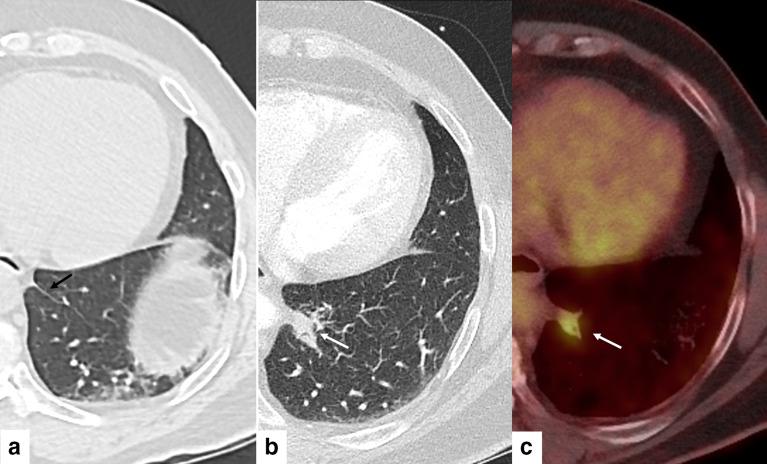

The inferior pulmonary ligament and related connective tissue septa are a recognizable site of granulomatous lymphadenitis on CT of the chest and may mimic a lung parenchymal lesion. The anatomy of the inferior pulmonary ligament, CT appearances and potential etiologies of this entity are reviewed and illustrated.

肺下韧带及相关结缔组织间隔是胸部CT上肉芽肿性淋巴结炎的一个可识别部位,可能酷似肺实质病变。本文回顾并举例说明了肺下韧带的解剖结构、CT表现及该病变的潜在病因。